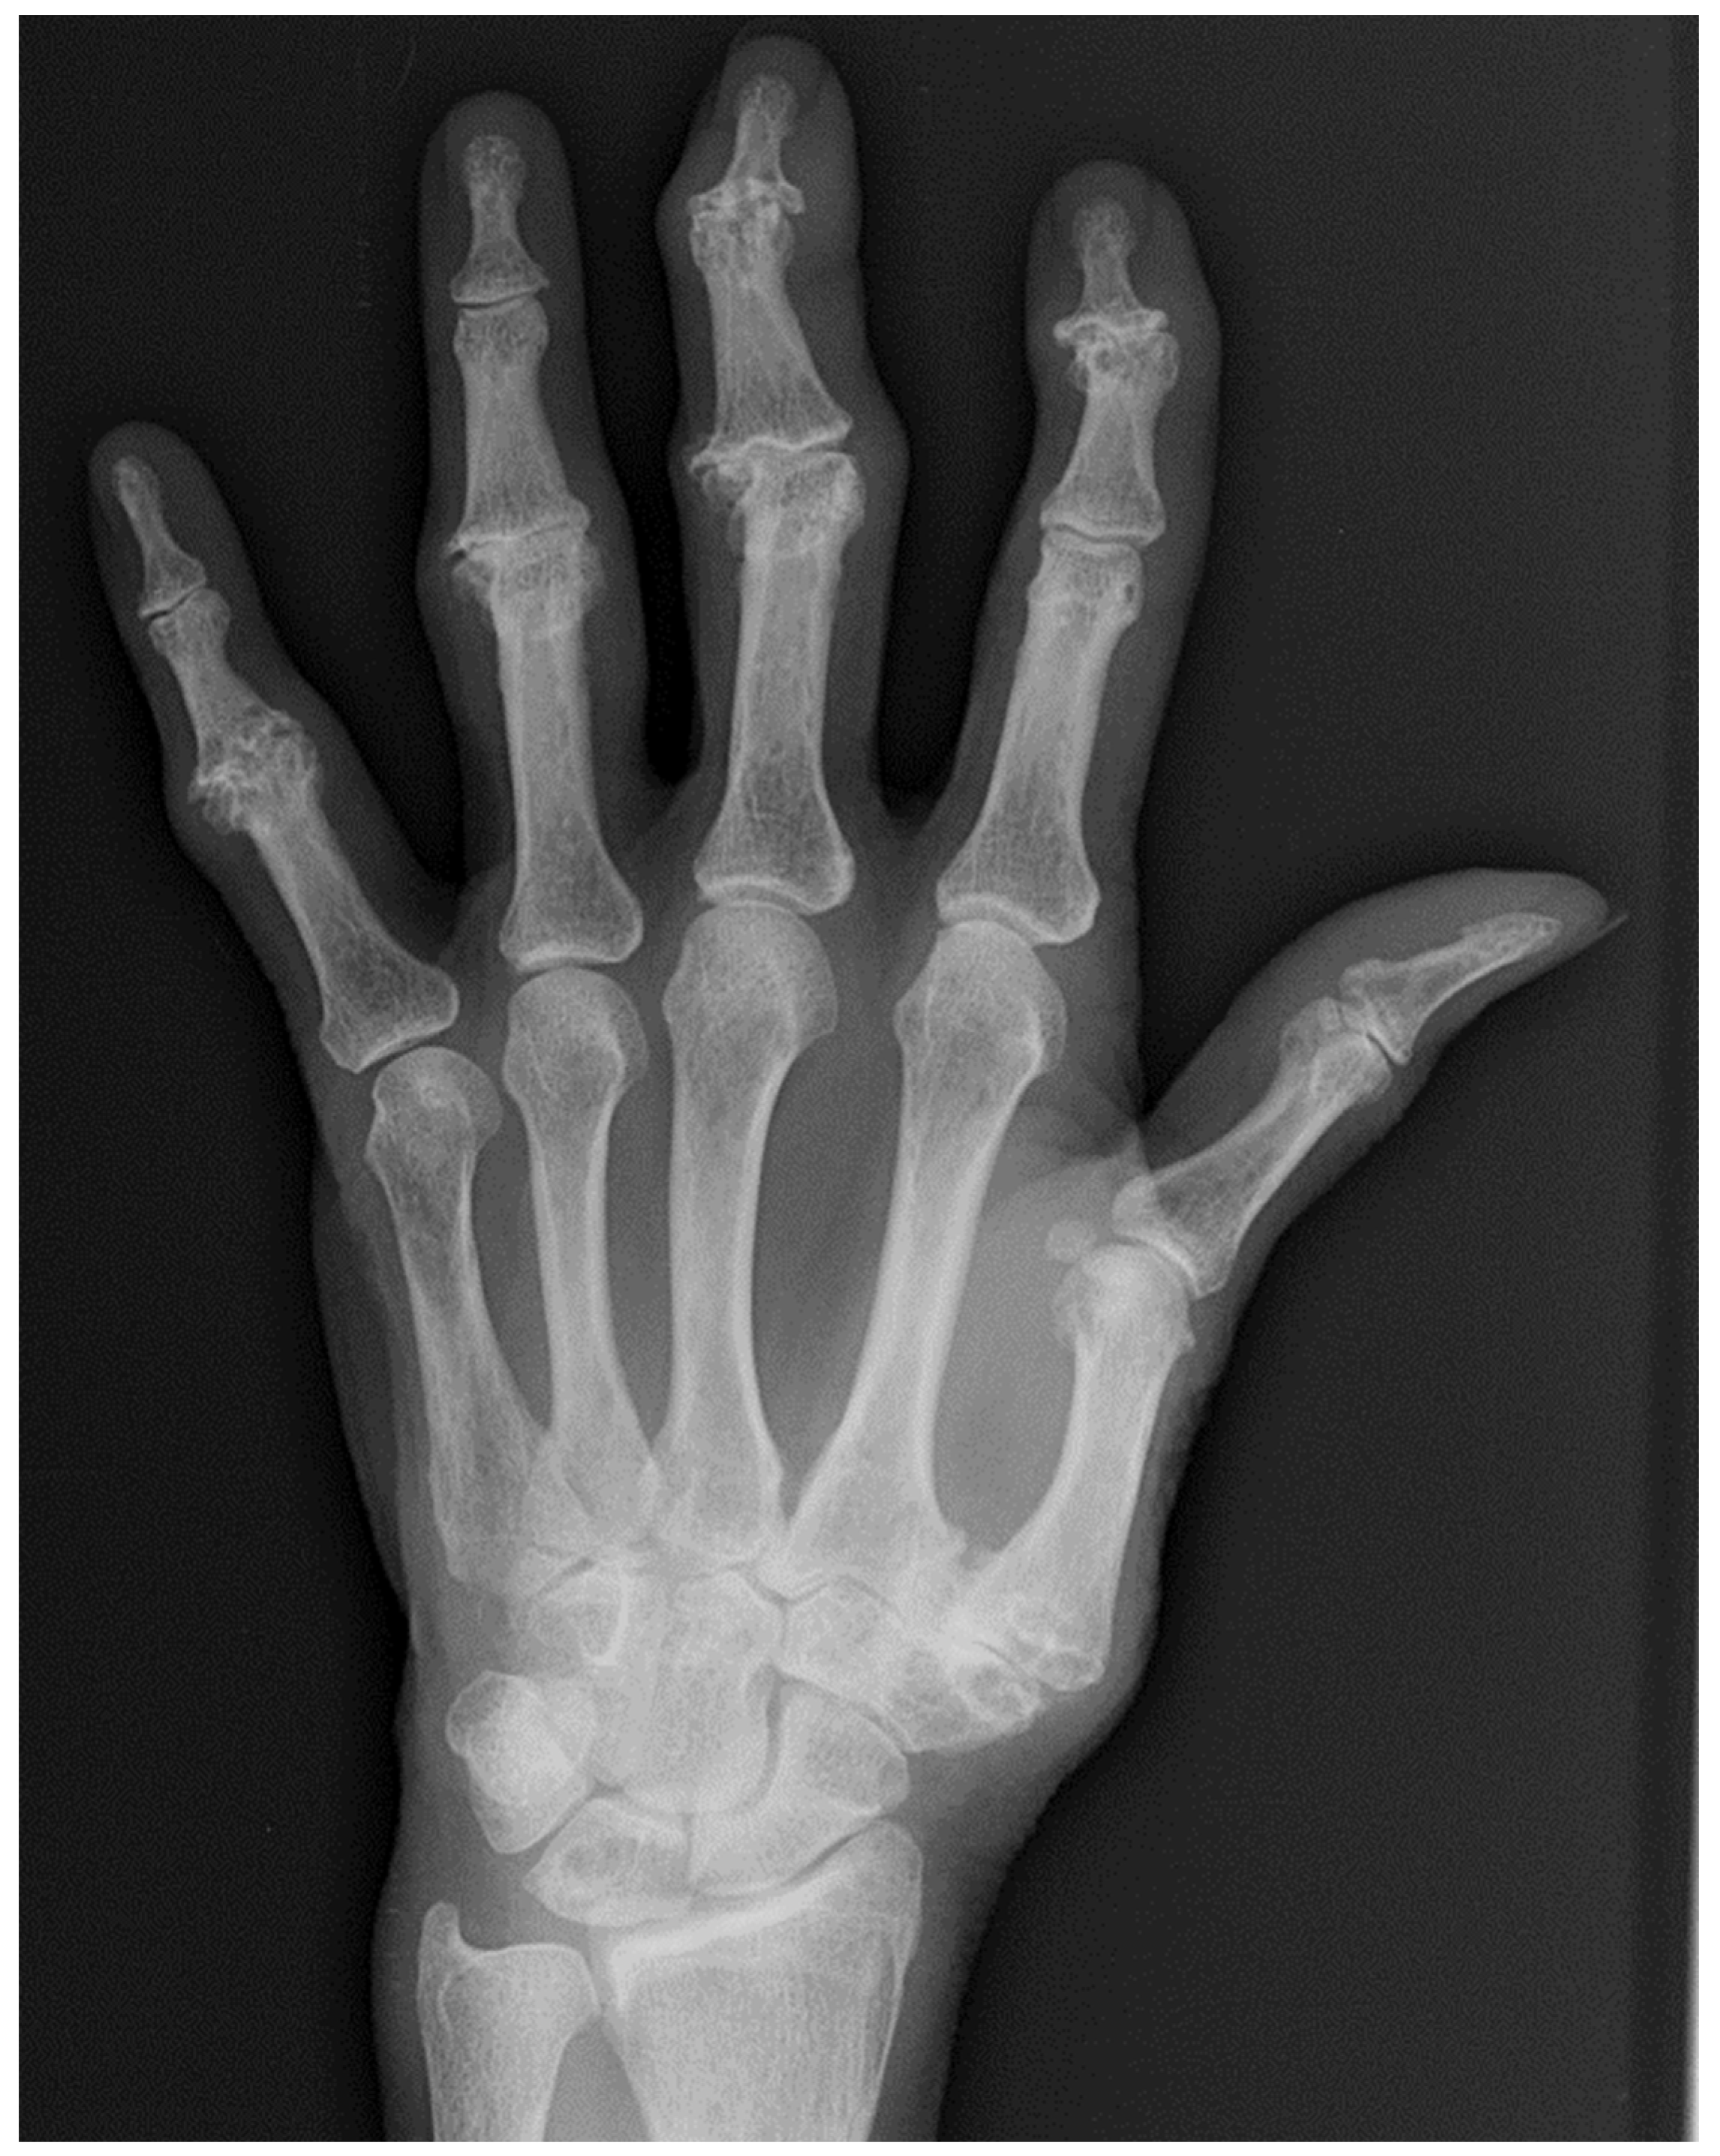

5. Psoriatic Arthritis (PsA)